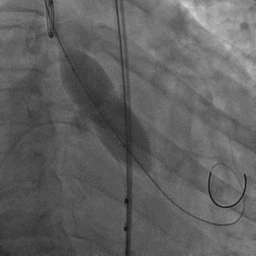

TAVR手术治疗通常需要使用两侧股动脉作为一主一副两条入路进行手术,主入路用于输送瓣膜等器械,副入路用于造影定位;在进行简化探索后,也可以使用桡动脉代替股动脉作为副入路,减少患者痛苦。经过熟练的极简式操作后,安贞医院瓣膜介入中心宋光远团队再次探索进一步简化TAVR操作,取消副入路,将造影导管同时置于主入路鞘管的“All in one”技术。并在同一天使用目前国内三家上市的国产自膨式TAVR瓣膜,证实三家瓣膜输送系统均可以采用“All in one”技术。

“All in one”技术示意:将瓣膜输送器与5F造影猪尾导管同时置于20F鞘管中